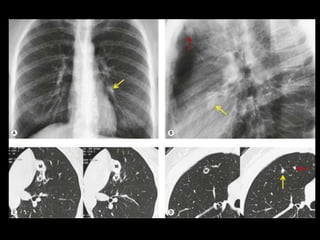

Malformação arteriovenosa(MAV) TC:o aspecto típico é de uma massa regular, lobulada, redonda ou oval, ou até o de uma formação serpenginosa, com menos de 1 cm a vários cm de tamanho, associada a uma artéria nutriz visivelmente aumentada e uma veia de drenagem alargada; Uma ANGIO-TC geralmente faz o diagnóstico; Tratamento pode ser realizado com terapia embólica.

• 19.

MAV complexa